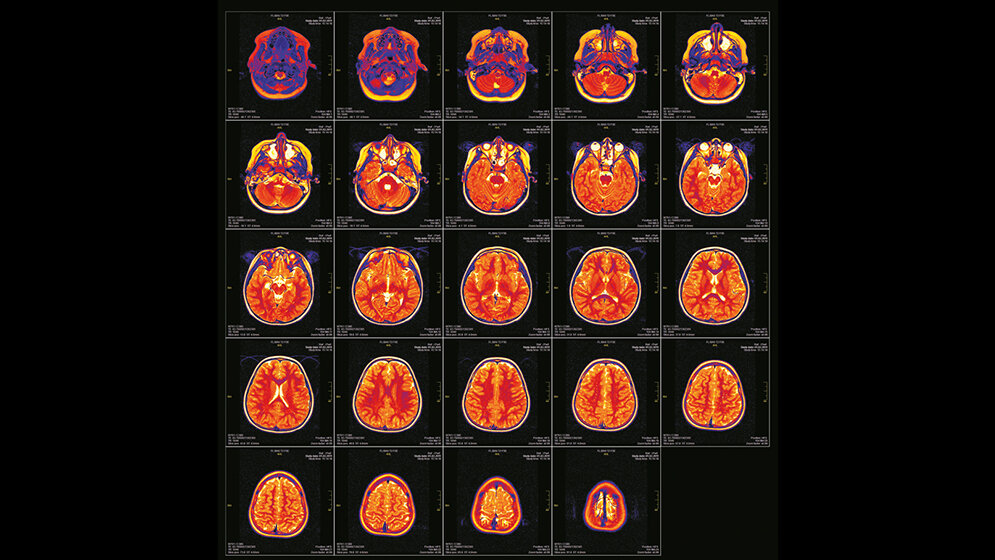

Entnommen aus MTA Dialog 01/2015